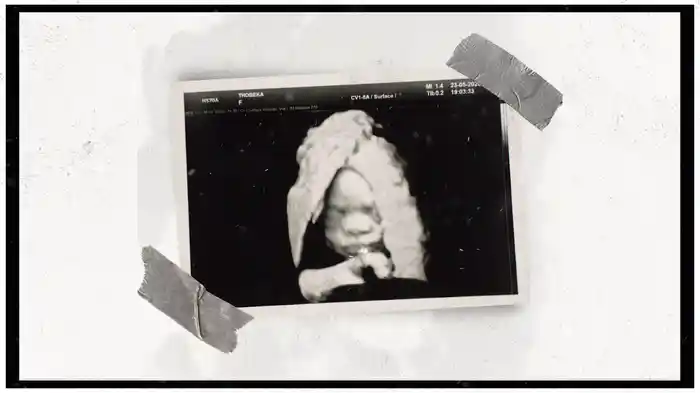

Celebrate (Visualizer)